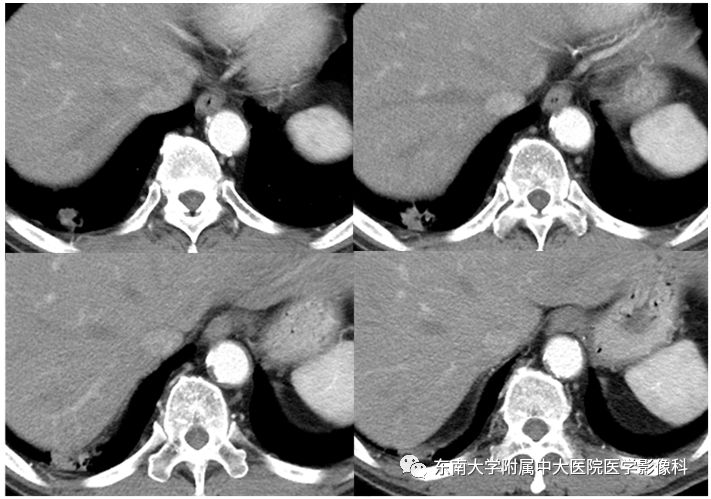

男,70岁,因“腹痛2月余,发现胃窦病变9天”入院

病例结果:病例1:机化性肺炎;病例2:肺腺癌